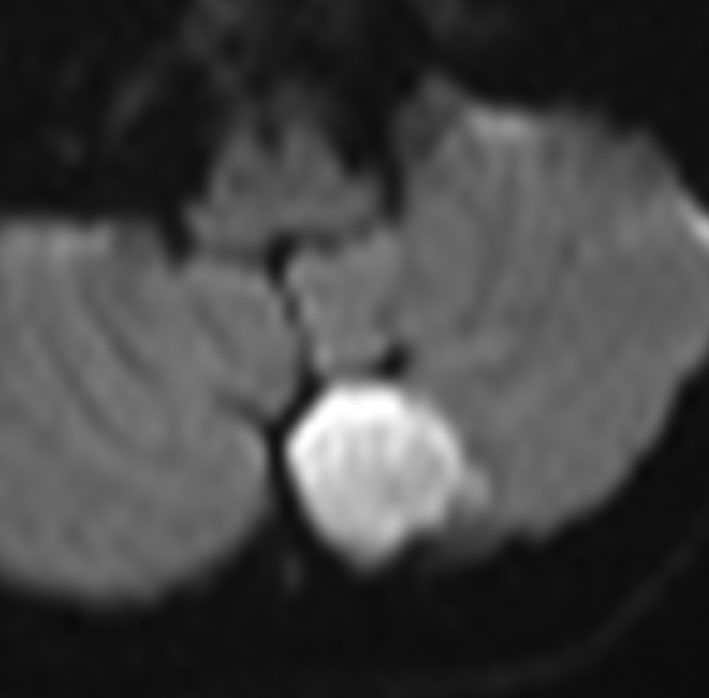

この画像は拡散強調画像 DWI と言います。左が術前,右が術後です。拡散強調画像 DWIで強い高信号になるのが特徴です。しかし,類表皮のう胞でも高信号になるので注意を要します。